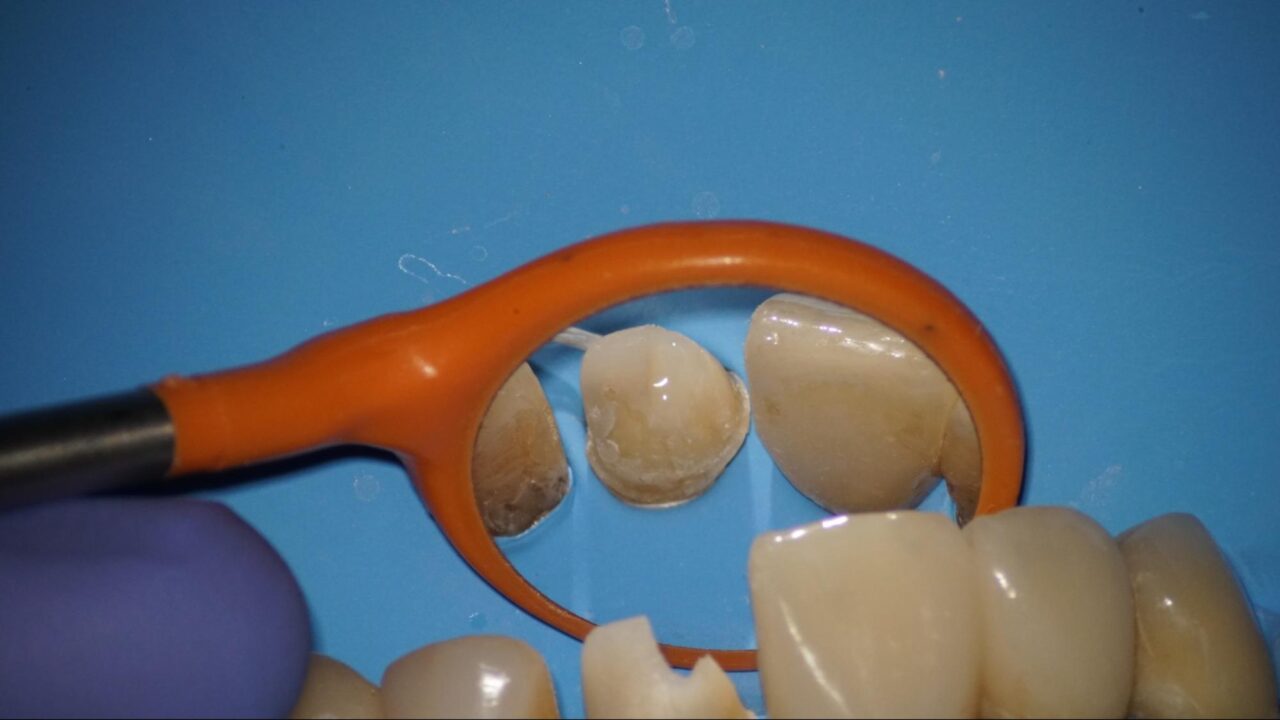

症例1:外傷による歯髄炎から抜髄処理

レントゲン像から外傷による歯髄炎を起こして抜髄処置を行ないました。(術前の口腔内写真、レントゲン)

術前レントゲン写真、隣の歯も外傷による歯根破折がレントゲンから確認できます。

麻酔をしてラバーダム防湿を行い、可能な限り健全歯質の温存を考慮しながら、歯髄を除去していきます。